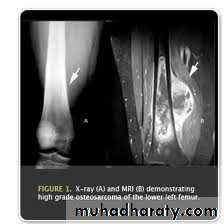

MRI

Allow accurate delination of the tumor size and the extent of invasion to the near soft tissue.

And the extension in to the medullary canal (skipped lesion).CT and chest radiograph is mandatory for preoperative staging